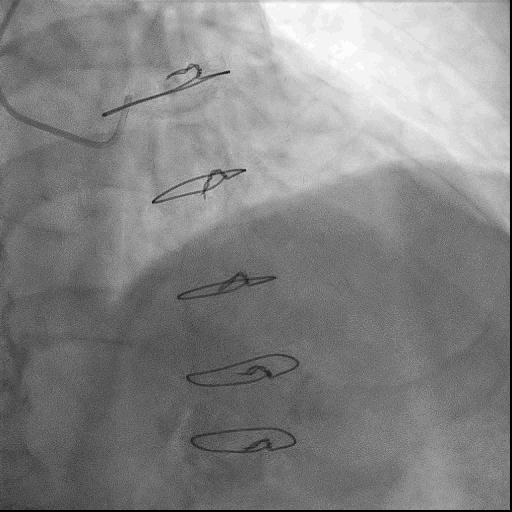

术前冠脉造影

RCA自近端齐头闭塞,无残端,远端隐约可见自身侧支形成,后三叉显影不佳

左侧LIMA-LAD、SVG-OM1桥血管通畅

右侧SVG-RCA桥血管闭塞